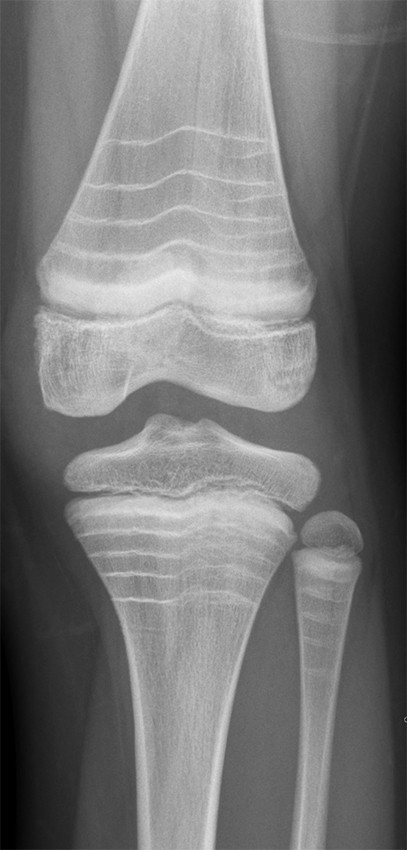

Røntgenbiletet viser eit kne med multiple, tverrgåande, sklerotiske (kvite) linjer i metafysen både i femur og tibia hos ein gut i tenåra. Pasienten har også tilsvarande funn i fleire andre ledd. Han har diagnosen osteogenesis imperfecta type 1 og har i fem år fått intravenøs behandling med zoledronsyre (bisfosfonat). Kvar av dei tverrgåande linjene svarer til ein behandlingsrunde/injeksjon med bisfosfonat. Hyppigare injeksjonar gjev kortare avstand mellom linjene. Linjene er vanlegast i metafysane, men kan også finnast i epi- og apofysane. Desse sklerotiske linjene er resultat av auka beinmineralisering (1) og er ein indirekte respons på hemming av osteoklastaktivitet som følge av behandlinga. I 2007 kom eit forslag om å nemne desse forandringane for sebralinjer (zebra lines) (2).

Osteogenesis imperfecta er ein medfødd kollagensjukdom som særleg påverkar skjelettet, men også bindevevsstrukturane i kroppen. Osteogenesis imperfecta vert klassifisert i fem grupper med ulik genetisk årsak og alvorsgrad. Type 1 er den vanlegaste og mildaste forma. Felles er at syntesen av kollagenfiber er unormal enten i høve til mengde fiber eller ved endringar av kollagenstrukturen. Dette gjer at m.a. skjelettet vert svakare overfor mekanisk belastning, og dermed aukar risikoen for beinbrot, skjelettsmerter og deformering av skjelettet (3). Det er inga kurativ behandling for sjukdommen. Behandlinga er tverrfagleg og målretta for å redusere brotrisiko og komplikasjonar ved brot og for å fremme ei så normal fungering som mogleg.

Medikamentell behandling med intravenøs bisfosfonat vert vurdert ut frå brothistorikk og alvorsgrad. Bisfosfonatbehandling aukar mineraliseringa av beinvevet, men påverkar ikkje sjølve kollagenfeilen. Zoledronsyre vert gitt kvar sjette månad frå toårsalderen og vanlegvis fram til barnet er ferdig med å vekse, men behandlingslengda vert vurdert individuelt. Zoledronsyre er ikkje godkjent til bruk under to års alder, så før det nyttar ein difor månadlege infusjonar med pamidronat.